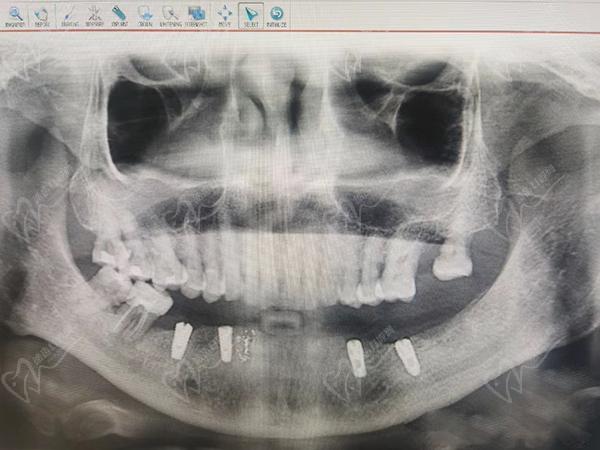

柯威爾種植體在韓國(guó)種植體排名前三位置,是韓國(guó)植體中的高端品牌,臨床反饋數(shù)據(jù)好,做半口、全口種植牙成效更好,愈合也更快。